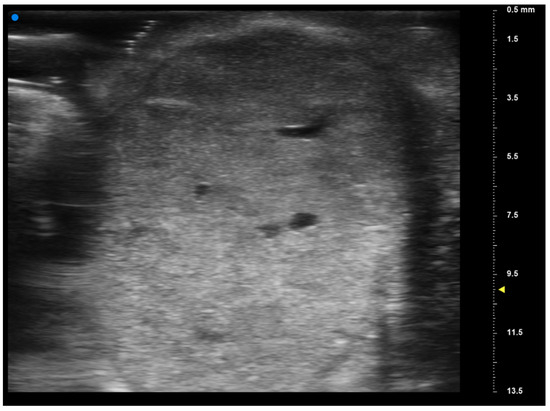

Reliability of Ultrasonographic Assessment of Depth of Invasion and Tumor Thickness in Intraoral Mucosa Lesions: A Preliminary Experience

2.2. UHFUS Scan Protocol